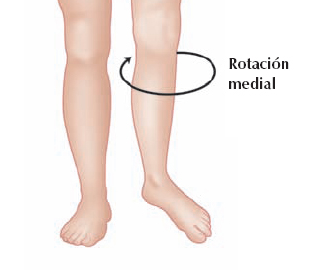

- Las características biomecánicas más relevantes son un aumento de la basculación anterior de la pelvis y una rotación medial de la rodilla.

Rotación medial de la rodilla